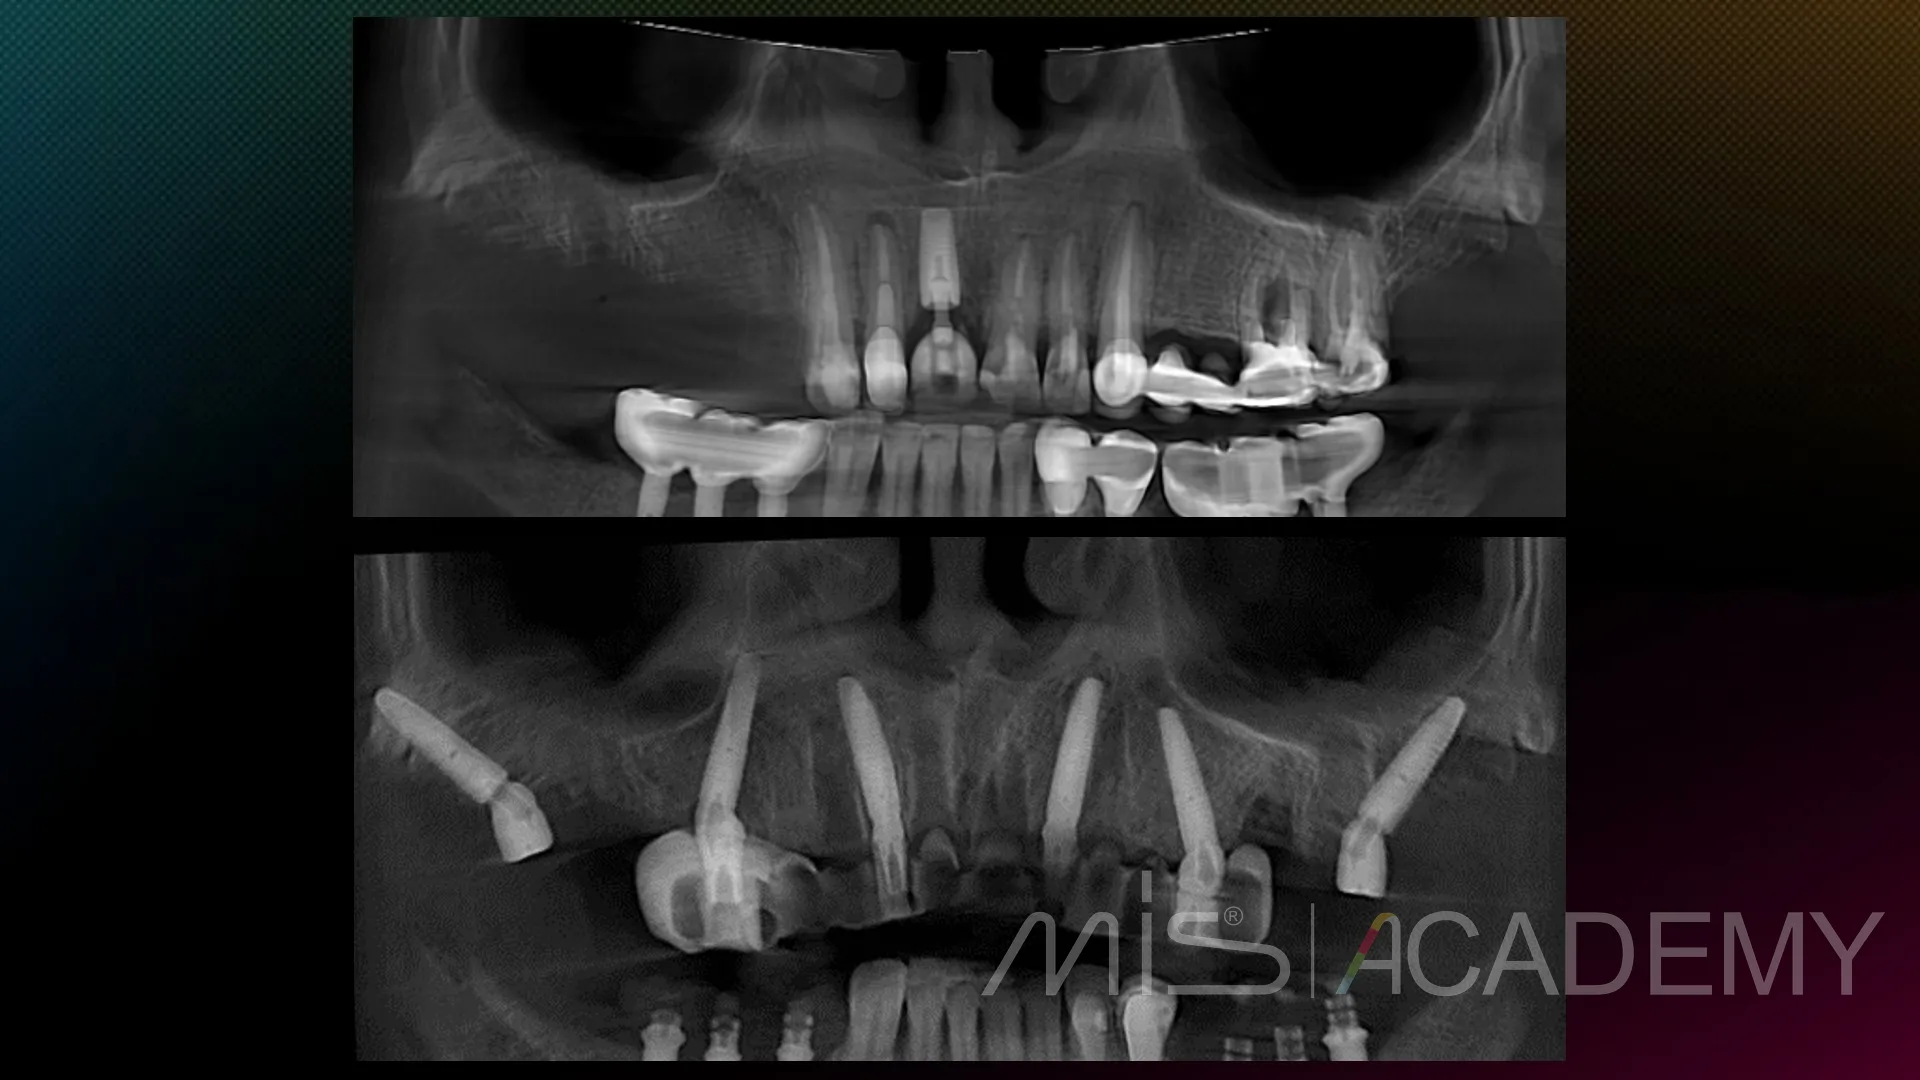

Промежуточный этап тотальной реабилитации.

Сделано:

1. Снятие несостоятельных реставраций на н/ч

2. MockUp на нижние передние зубы, новые временные протезы на имплантаты, установленные 7 лет назад, на новой высоте прикуса.

3. Удаление зубов на в/ч, установка 6 имплантатов MIS C1 по навигационному шаблону, мультиюнит абатменты, CONNECT абатменты в переднем отделе, в лунки — bio-oss, стимул-осс, пластика десны.

4. Временный протез в день операции.

5. Контрольные осмотры на 4 и 14 сутки.